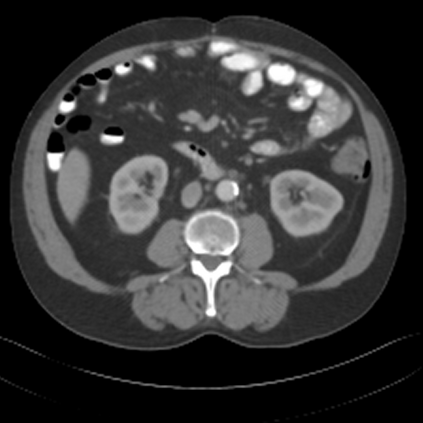

Sparse-view computed tomography (CT) -- using a small number of projections for tomographic reconstruction -- enables much lower radiation dose to patients and accelerated data acquisition. The reconstructed images, however, suffer from strong artifacts, greatly limiting their diagnostic value. Current trends for sparse-view CT turn to the raw data for better information recovery. The resultant dual-domain methods, nonetheless, suffer from secondary artifacts, especially in ultra-sparse view scenarios, and their generalization to other scanners/protocols is greatly limited. A crucial question arises: have the image post-processing methods reached the limit? Our answer is not yet. In this paper, we stick to image post-processing methods due to great flexibility and propose global representation (GloRe) distillation framework for sparse-view CT, termed GloReDi. First, we propose to learn GloRe with Fourier convolution, so each element in GloRe has an image-wide receptive field. Second, unlike methods that only use the full-view images for supervision, we propose to distill GloRe from intermediate-view reconstructed images that are readily available but not explored in previous literature. The success of GloRe distillation is attributed to two key components: representation directional distillation to align the GloRe directions, and band-pass-specific contrastive distillation to gain clinically important details. Extensive experiments demonstrate the superiority of the proposed GloReDi over the state-of-the-art methods, including dual-domain ones. The source code is available at https://github.com/longzilicart/GloReDi.